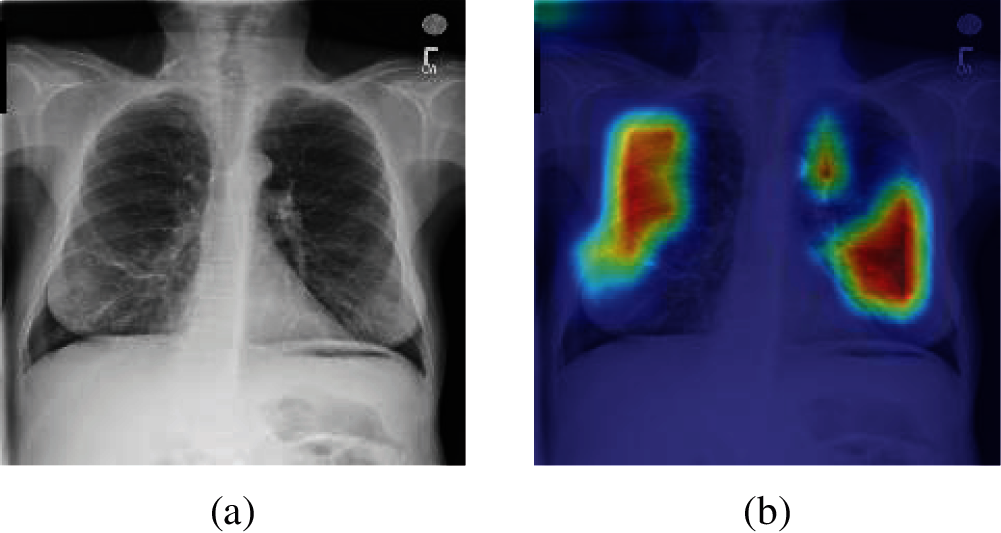

To better understand the performance of different methods, Gradient-weighted Class Activation Mapping (Grad-CAM) is introduced. By analyzing the Grad-CAM result of original chest X-ray images of each method, we can more intuitively compare the detection performance between different methods. Fig. 12 shows the Grad-CAM result image of an original chest X-ray images. It is worth noting that the higher color brightness areas in Grad-CAM result image, the greater the output reference weight.

Figure 12: A sample of Grad-CAM result of the original chest X-ray images (a) A sample of the original Chest X-ray images (b) Grad-CAM result of (a)